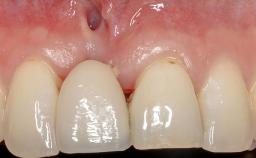

Implant Placement in the Esthetic Zone and Coverage of Multiple Gingival Recessions

This case illustrates use of a modified ‘tunnel’ technique, which has been shown to be highly effective in root coverage procedures. The tunnel technique is used to achieve soft-tissue augmentation across the anterior area, including the planned implant site, using collagen matrix as grafting material. The patient is a 47-year-old woman with high esthetic expectations. Her main concern was the appearance of the anterior teeth and their “elongation”.